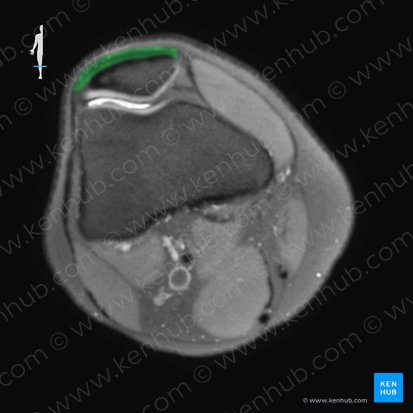

Das mediale Kollateralband (MCL), das Ligamentum collaterale tibiale, lässt sich am besten auf einem T2-Bild in der Koronalebene untersuchen. Dort ist es als langes, dünnes Band mit gleichmäßig niedriger Intensität auf der medialen Seite der Gelenkkapsel zu sehen. Es entspringt am medialen Epicondylus des Femurs und setzt an der medialen Metaphyse der Tibia an.

Auf einem Schnitt durch die interkondyläre Kerbe in der axialen Ebene können wir den Ursprungspunkt des MCLs finden. Dieser erscheint als kurzes, niedriges Signalband nahe der medialen Seite der Femurkondyle. Wenn wir weiter nach unten scrollen, können wir das MCL bis zu seinem Ansatz an der Tibia verfolgen.

Wie das mediale Kollateralband, ist auch das laterale Kollateralband (LCL), das Ligamentum collaterale fibulare, am besten auf einem T2-Bild in Koronalebene zu sehen. Dort erscheint es als homogene Struktur mit geringer Intensität auf der lateralen Seite der Gelenkkapsel. Das LCL entspringt am Epicondylus lateralis femoris und setzt zusammen mit der Biceps-femoris-Sehne am Fibulakopf an.

Betrachtet man das LCL in der Axialebene auf einem Schnitt durch die interkondyläre Kerbe, so kann man ihren Ursprung als ovales schwaches Signal in der Nähe des posterioren Aspekts der Femurkondyle erkennen. Wenn man nach unten scrollt, kann man dem LCL folgen, wie es an der anterolateralen Seite des Fibulakopfs ansetzt.